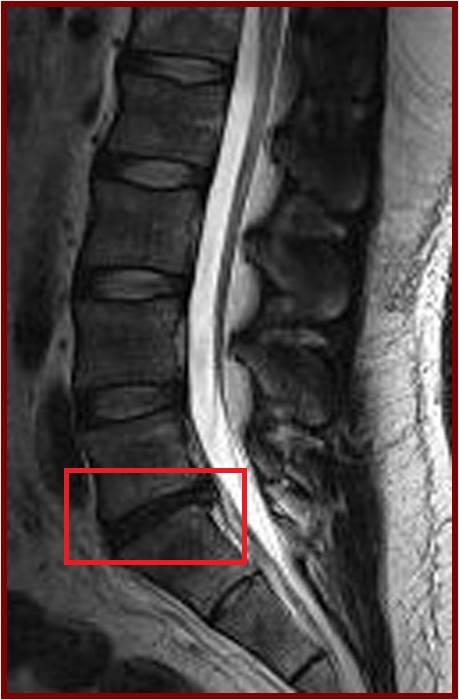

Low back pain affects every population worldwide, and is a leading cause of ill-health and sick leave in the working population of Hong Kong. One of the major causes of low back pain is degeneration of the joints of the spine, known as the intervertebral discs. A cohort study conducted by the Department of Orthopaedics & Traumatology at The University of Hong Kong Li Ka Shing Faculty of Medicine reveals that being obese in adulthood doubles the likelihood of having disc degeneration and developing more severe forms of the condition than those of normal weight. These findings are of public health concern and were published in the latest issue of the authoritative journal Arthritis and Rheumatism.

The current study was a cross-sectional assessment of adults from this cohort who were 21 years of age and older. A total of 2,599 individuals were assessed with magnetic resonance imaging (MRI). Amongst them, 27% (n=709) did not have disc degeneration while 73% (n=1,890) had. Of the subjects who have disc degeneration, 7% were underweight, 48% were in the normal weight range, 36% were overweight, and 9% were obese. Overweight and obese individuals were also found to have a greater extent and severity of disc degeneration in comparison to those individuals of normal weight or underweight.